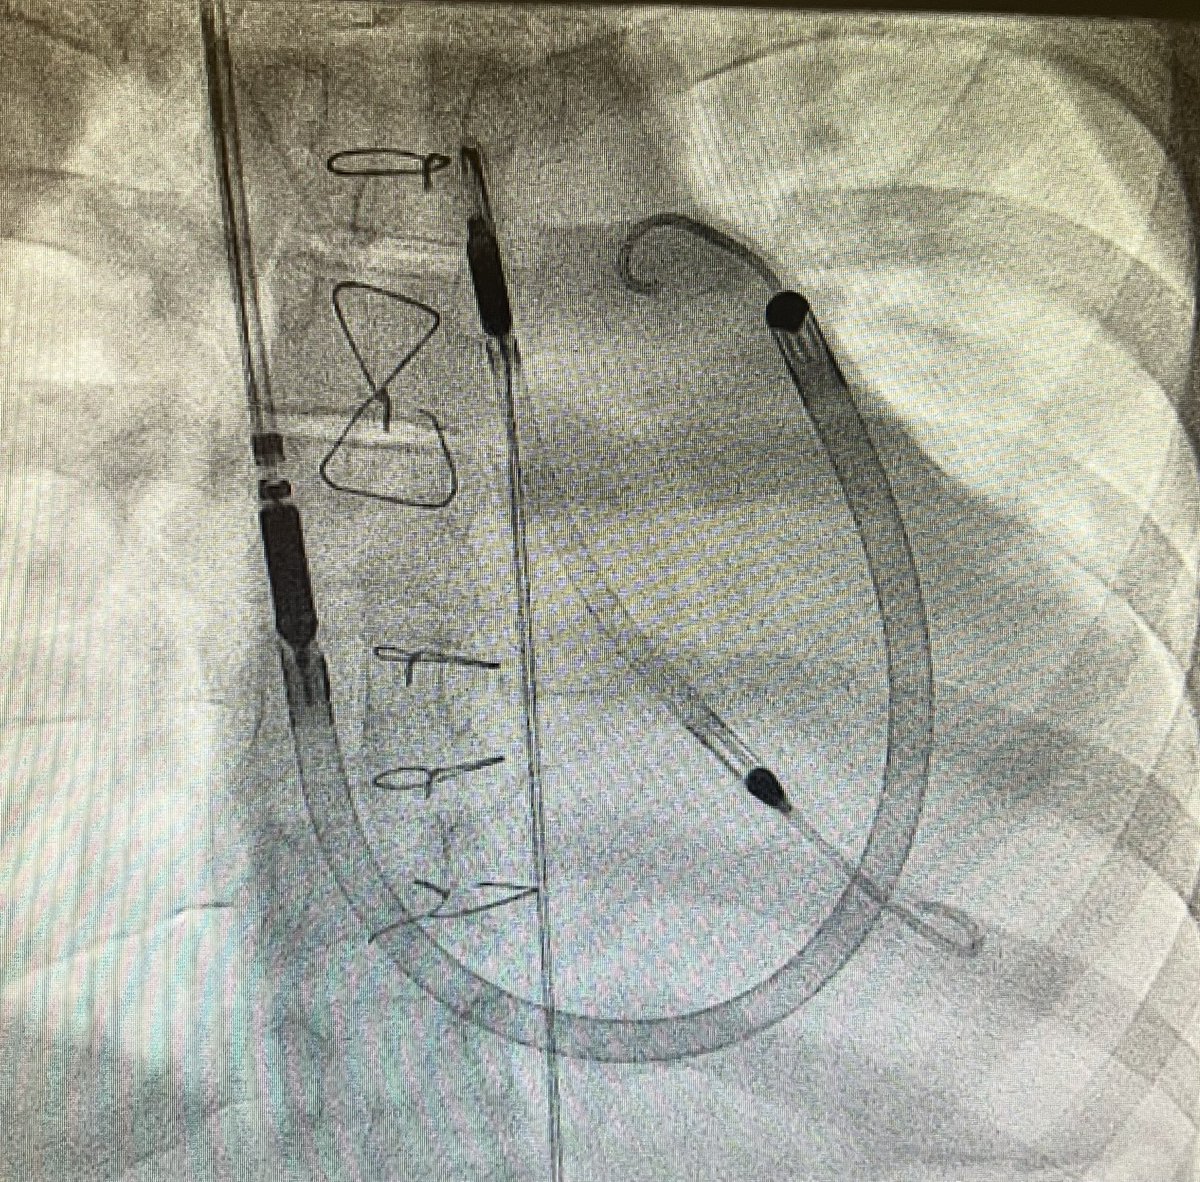

Biventricular mechanical support without surgery?! Teenager in cardiogenic shock with severe BiV dysfunction and acute end organ injury supported w/ #Impella CP and RP flex. No cutting necessary. #MCS #CHD #pedcards #cardionerds @CardioNerds @Adam_Skaff @SohamDasguptaMD

#Fontan patients offer unique challenges! Teenager with #HLHS post Fontan with recoarctation and LPA stenosis. LCA ran along the course of the LPA. Did coronary compression testing but able to stent both with good result. #CHD #ACHD @NCProvider @Adam_Skaff @SohamDasguptaMD 1/2

Good result and no coronary compression or change in coronary orientation